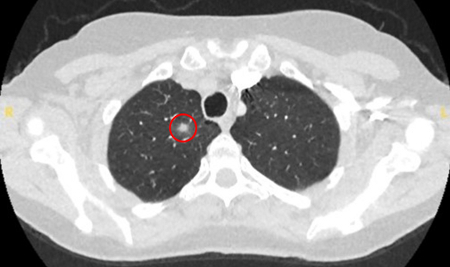

A causa mais provável de nódulos pulmonares solitários benignos dependerá da epidemiologia local da doença. Por exemplo, num centro acadêmico dos EUA, 23% dos pacientes submetidos à ressecção de um nódulo suspeito apresentaram patologia benigna, com doença granulomatosa, como tuberculose e infecções fúngicas (por exemplo, histoplasmose, coccidioidomicose, aspergilose), identificadas como a causa mais comum.[10] Granulomas não infecciosos geralmente devem-se à granulomatose com poliangiite (antes conhecida como granulomatose de Wegener), sarcoidose ou artrite reumatoide.[Figure caption and citation for the preceding image starts]: Tomografia computadorizada (TC) mostrando nódulo cavitante posterior no lobo superior direito, com biópsia confirmando granulomatose com poliangiiteDo acervo de Dr. George Tsaknis, MD, PhD, FRCP (Londres), MRQA, MAcadMEd, PGCert; usado com permissão [Citation ends].